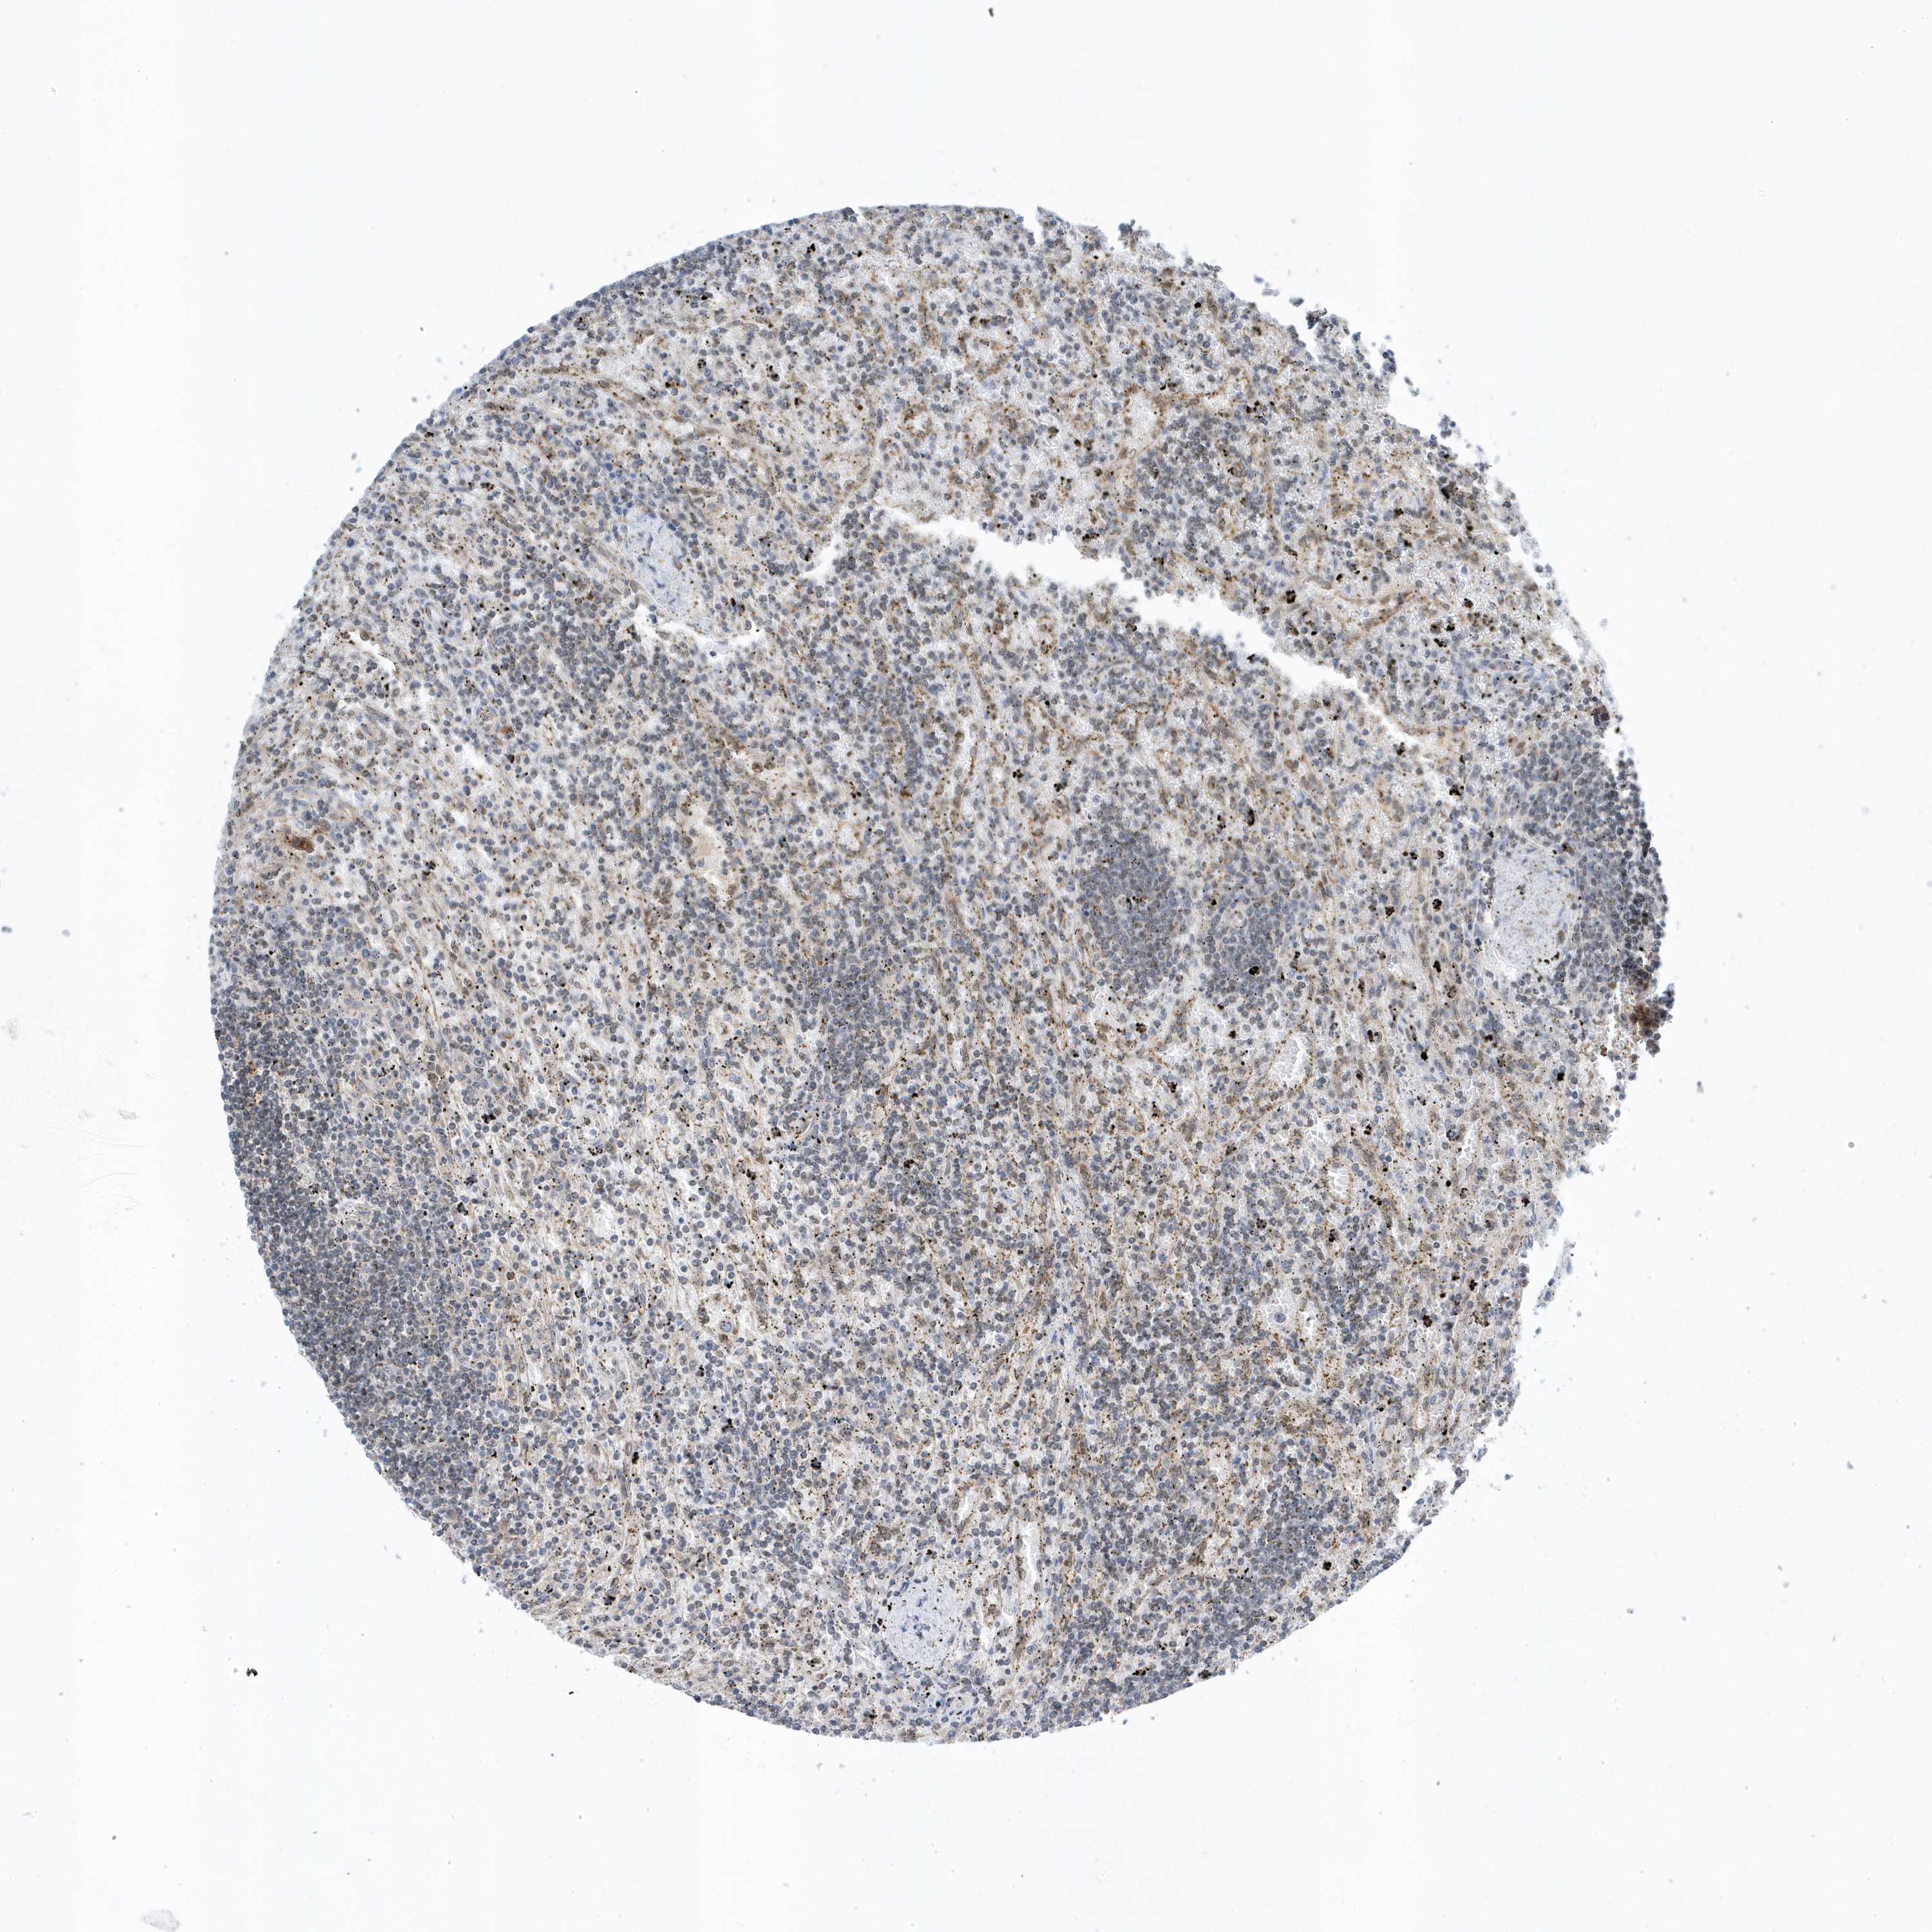

LYMPHOMA - Protein expressioni

A mouse-over function shows sample information and annotation data. Click on an image to view it in a full screen mode. Samples can be filtered based on level of antibody staining by selecting one or several of the following categories: high, medium, low and not detected. The assay and annotation is described here.

Antibody stainingi

Antibody staining in the annotated cell types in the current human tissue is reported as not detected, low, medium, or high, based on conventional immunohistochemistry profiling in selected tissues. This score is based on the combination of the staining intensity and fraction of stained cells.

Each image is clickable and will lead to virtual microscopy that enables deeper exploration of all samples and also displays staining intensity scores, fraction scores and subcellular localization as well as patient and tissue information for each sample.

Antibody HPA035691

Staining

High

Medium

Low

Not detected

Intensity

Strong

Moderate

Weak

Negative

Quantity

>75%

75%-25%

<25%

None

Location

Nuclear

Cytoplasmic/membranous

Cytoplasmic/membranous,nuclear

Hodgkin's disease, NOS

Malignant lymphoma, non-Hodgkin's type, High grade

Malignant lymphoma, non-Hodgkin's type, Low grade